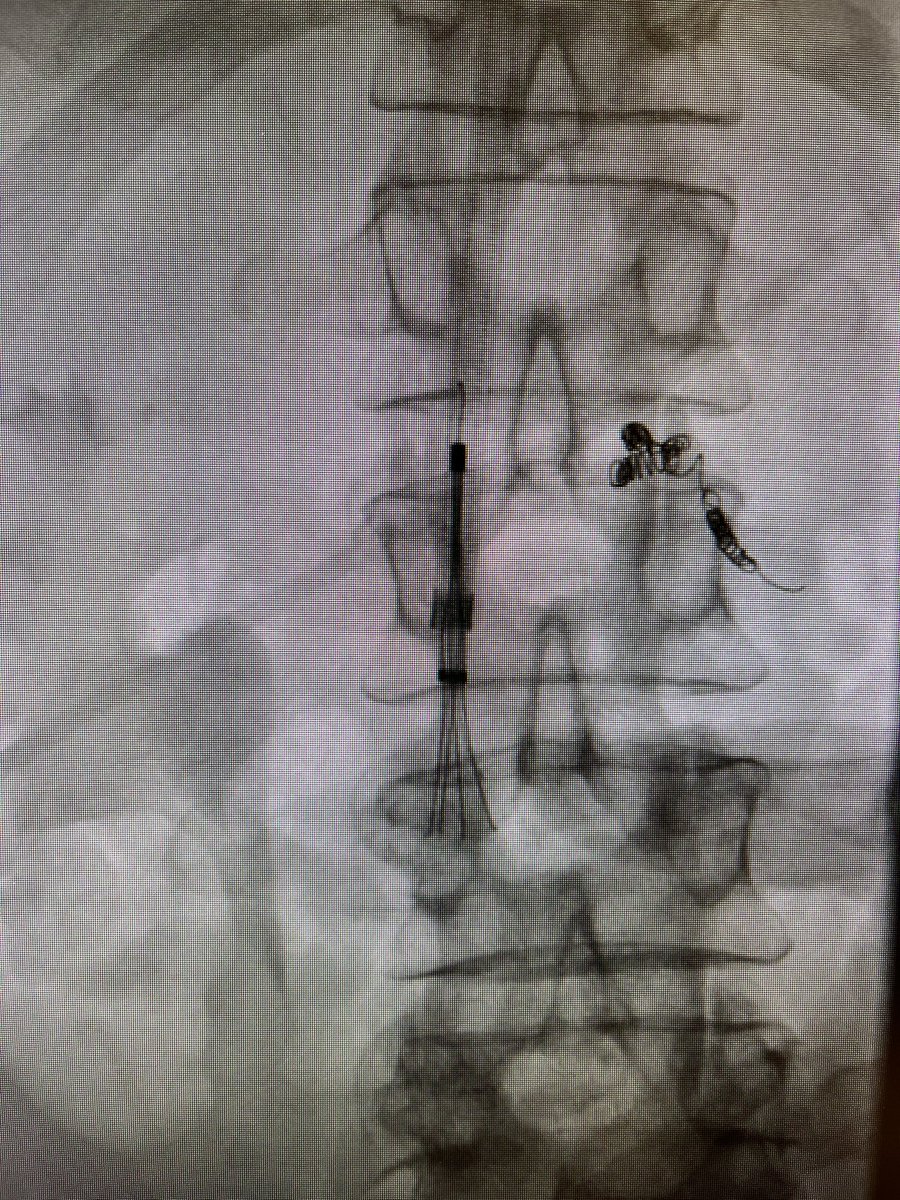

One of the 1st studies in healthcare using @HoloLens 2, supported by @RSNA. #AugmentedReality guidance improves procedure times and radiation dose. Med students also instantly elevated to #IRAD attending level! @dotter_IR @Penn_IR @PigiLab @SIRRFS rdcu.be/b9p98